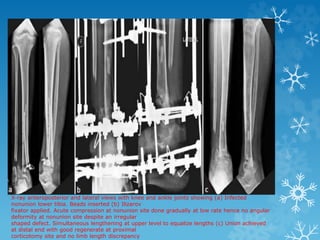

X-ray anteroposterior and lateral views with knee and ankle joints showing (a) Infected

nonunion lower tibia. Beads inserted (b) Ilizarov

fixator applied. Acute compression at nonunion site done gradually at low rate hence no angular

deformity at nonunion site despite an irregular

shaped defect. Simultaneous lengthening at upper level to equalize lengths (c) Union achieved

at distal end with good regenerate at proximal

corticotomy site and no limb length discrepancy

X-ray anteroposterior andlateral views with knee and ankle joints showing (a) Infected nonunion lower tibia. Beads inserted (b) Ilizarov fixator applied. Acute compression at nonunion site done gradually at low rate hence no angular deformity at nonunion site despite an irregular shaped defect. Simultaneous lengthening at upper level to equalize lengths (c) Union achieved at distal end with good regenerate at proximal corticotomy site and no limb length discrepancy